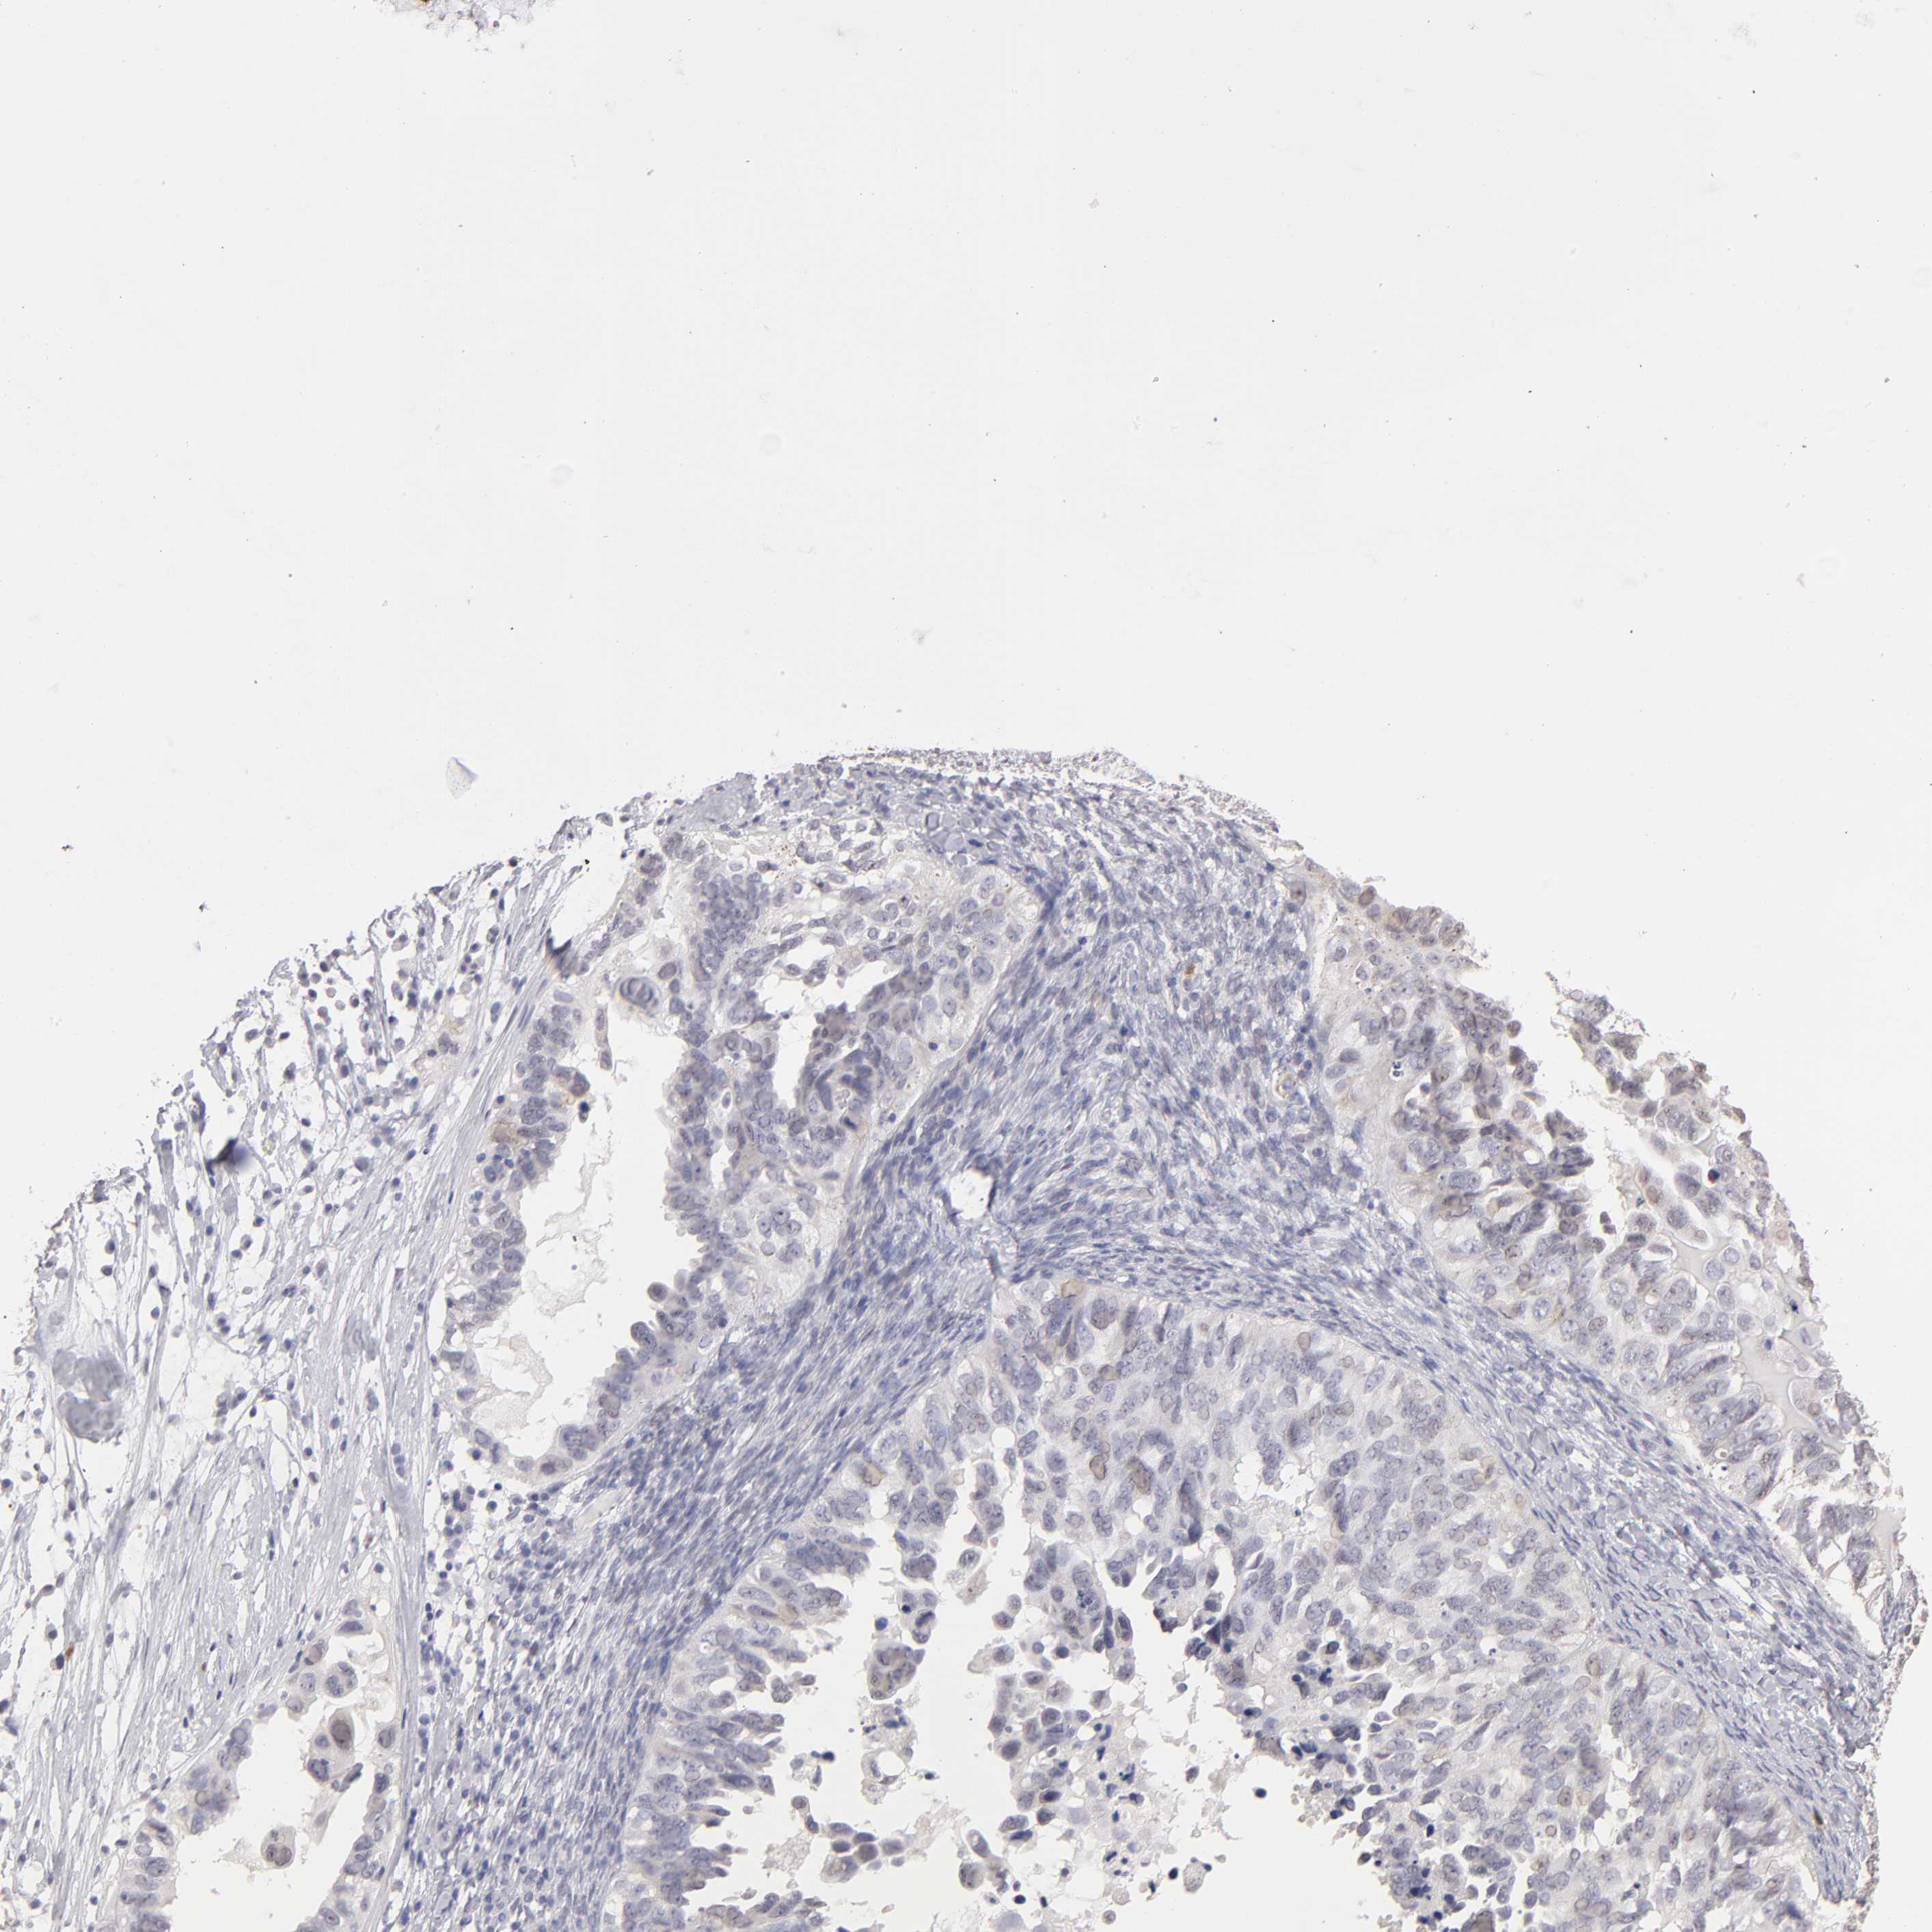

OVARIAN CANCER - Protein expressioni

A mouse-over function shows sample information and annotation data. Click on an image to view it in a full screen mode. Samples can be filtered based on level of antibody staining by selecting one or several of the following categories: high, medium, low and not detected. The assay and annotation is described here.

Note that samples used for immunohistochemistry by the Human Protein Atlas do not correspond to samples in the TCGA dataset.

Antibody stainingi

Antibody staining in the annotated cell types in the current human tissue is reported as not detected, low, medium, or high, based on conventional immunohistochemistry profiling in selected tissues. This score is based on the combination of the staining intensity and fraction of stained cells.

Each image is clickable and will lead to virtual microscopy that enables deeper exploration of all samples and also displays staining intensity scores, fraction scores and subcellular localization as well as patient and tissue information for each sample.

Antibody HPA002270

Staining

High

Medium

Low

Not detected

Intensity

Strong

Moderate

Weak

Negative

Quantity

>75%

75%-25%

<25%

None

Location

Nuclear

Cytoplasmic/membranous

Cytoplasmic/membranous,nuclear

Cystadenocarcinoma, serous, NOS

Cystadenocarcinoma, mucinous, NOS

Carcinoma, endometroid